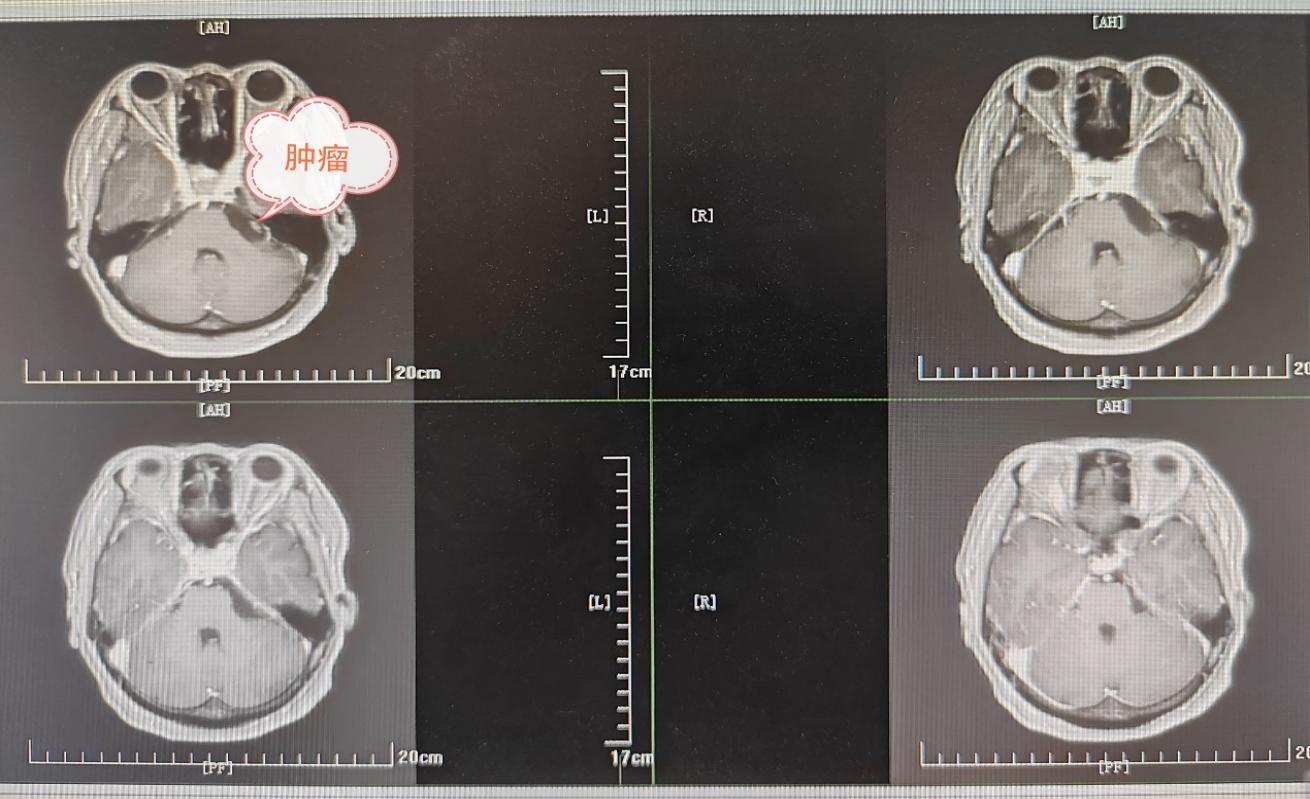

患者为中年女性,以面部疼痛症状入院,面对三叉神经痛为症状患者,经过检查,发现患者为右侧桥小脑角区长有一约4*1.5cm肿瘤。肿瘤沿桥小脑角间隙生长,最深部到达桥脑腹侧,包绕岩静脉、基底动脉、小脑上动脉、小脑前下动脉等重要血管和动眼神经、外展神经、面神经、听神经、舌咽神经等重要颅神经,桥小脑角区域解剖关系复杂,肿瘤沿缝隙生长,常规显微镜手术很难全切肿瘤。在缪星宇主任主持下,神经外科全科经过充分术前讨论后制定了精密诊疗方案,决定采用“双镜联合技术”切除肿瘤,这是国内部分先进医疗中心探索应用的技术,显微镜联合应用神经内镜,发挥最大优势;以显微镜清晰的三维成像为基础,利用神经内镜抵近观察和绕角观察的特性暴露深部肿瘤,既能发现并全切深部间隙隐藏肿瘤,又能在神经内镜直视下精准保护重要神经血管。手术由缪星宇主任医师、孟发财副主任医师、刘凯飞主治医师共同完成,经过5小时紧张有序的手术,血管神经保护良好,患者颅内肿瘤顺利全切,术后复查肿瘤全切,患者恢复良好出院。